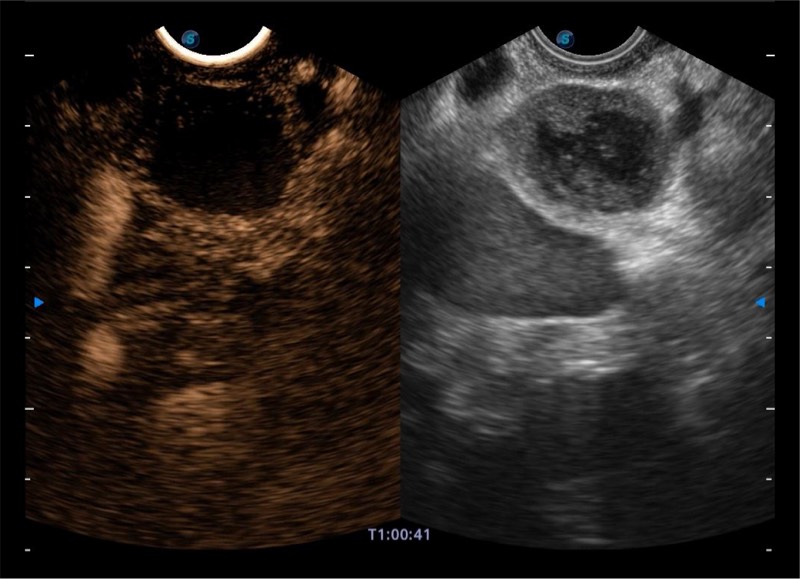

高端超声影像平台

基于二十年的超声技术积累,DB中国旗舰官方网站提供了最新一代的独立超声主机,在提供高质量图像的同时满足多学科使用。具备常见多普勒技术并提供弹性成像、声学造影等高端影像技术。新一代传感器具有更强的抗干扰能力并减少图像伪影。